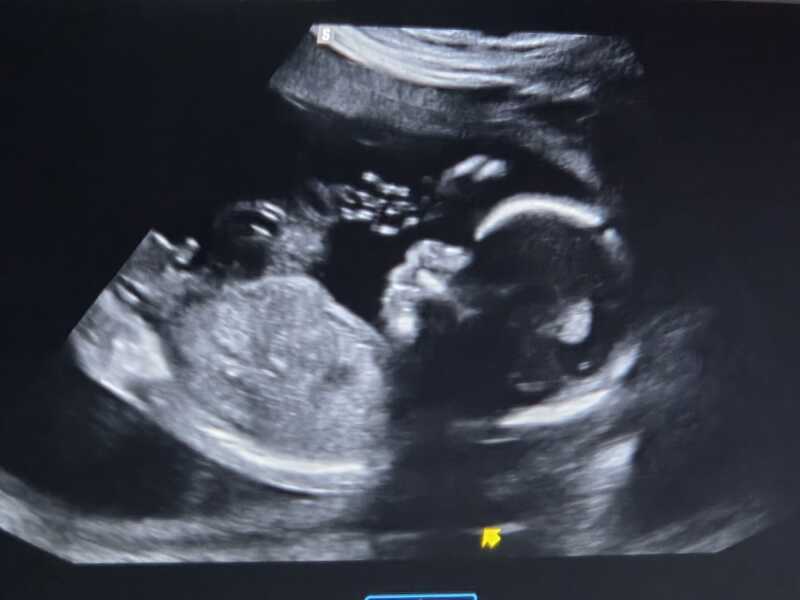

Skull theory says its a girl. This is the baby at 20 weeks. What are your guesses?

Girl

Boy. Didnt they tell you at the scan?

Boy